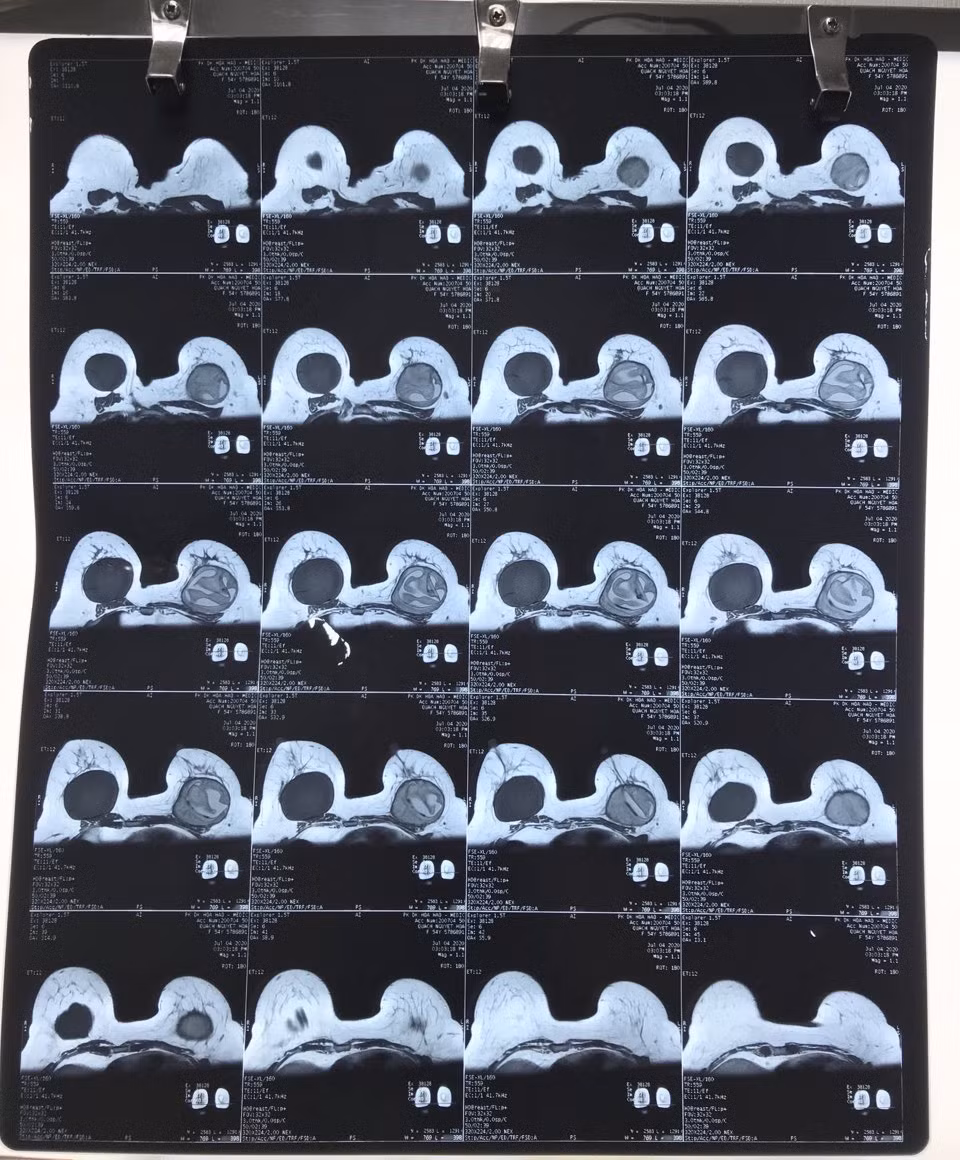

Hình chụp X-quang cho thấy túi ngực nhân tạo của chị H bị vỡ

Tại đây, bác sĩ cho biết chị H. bị vỡ túi ngực nhân tạo bên trái, nách trái có hạch lớn, bầu ngực bị biến dạng. Chị được bác sĩ tư vấn phẫu thuật lấy bỏ túi độn ngực hai bên, đồng thời làm xét nghiệm giải phẫu hạch và bao xơ xung quanh túi ngực để tầm soát ung thư vú. Với nguyện vọng có được "vòng 1" căng đẹp, chị H. xin ý kiến bác sĩ về việc đặt lại túi độn ngực.

BSCKII. Vũ Hữu Thịnh – Quản lý và điều hành, Phó trưởng Khoa Tạo hình – Thẩm mỹ BV ĐHYD TPHCM cho biết: "Túi ngực bên trái của người bệnh bị vỡ hoàn toàn và không phải là vật liệu được Bộ Y tế cấp phép trong phẫu thuật nâng ngực. Chúng tôi thực hiện phẫu thuật lấy bỏ túi ngực ở cả hai bên. Sau khi làm sạch, lấy hạch và bao xơ quanh túi ngực làm sinh thiết lạnh (giải phẫu bệnh tức thời), kết quả cho thấy sức khỏe của chị H. bình thường, chúng tôi đặt túi ngực mới theo nguyện vọng của chị".